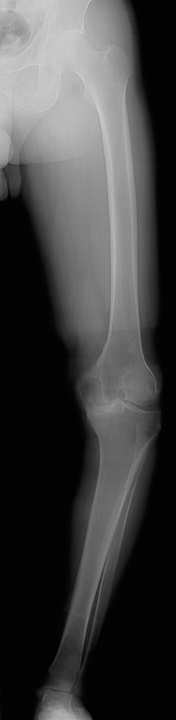

![]() 術前レントゲン |

人工膝関節置換術とは、傷んで変形した関節を人工の関節に置き換える手術です。人工関節の表面は滑らかで神経もないため、この手術を受けることによって、関節は滑らかに動くようになり、痛みもほとんど感じなくなります。また、O脚やX脚に変形した膝が、手術によって真っすぐな膝になります。痛みなく歩けるようになると、日常生活を送りやすくなり、生活の質(QOL)を改善することができます。

手術では、まず変形して傷んだ大腿骨と脛骨の表面の骨を切除します。大腿骨側と脛骨側の骨にそれぞれ金属製の人工関節(大腿骨・脛骨コンポーネント)を固定します。脛骨コンポーネントの上面に超高分子量ポリエチレン製の人工の軟骨(インサート)を設置します。人工膝関節は大腿骨コンポーネントとインサートの間で滑らかに動く構造になっています。